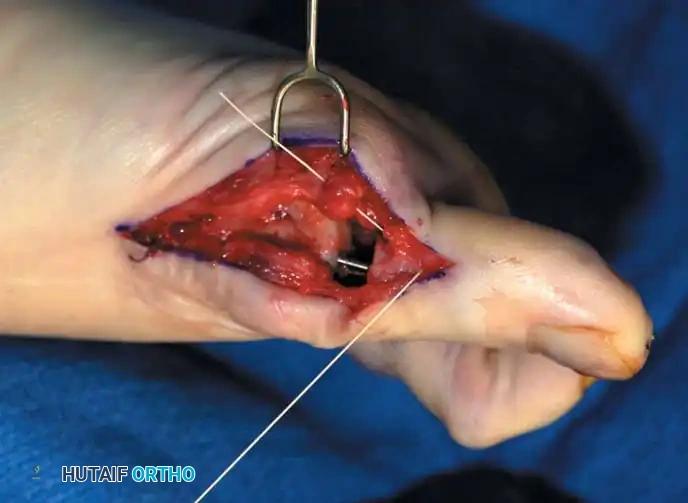

• Close the capsule with interrupted 2-0 or 3-0 absorbable sutures. A fi rm, complete capsular closure is imperative. A box stitch is recommended. Increasing the curve of the needle manually is helpful.

• Starting proximal and plantarward, pass the suture through the capsule from the outside in.

• The second pass of the suture is from the inside out through substantial soft tissue on the plantar medial aspect of the phalangeal base.

• Reenter the soft tissue at the base of the proximal phalangeal remnant dorsomedially for the third pass. Move the suture back and forth to ensure uninhibited excursion.

• Make the fourth pass from inside out through the dorsal capsule in line with the initial plantar capsular suture. Have an assistant grasp the ends of the capsule, pulling them together, while the tie is completed. This is basically a four-corner box stitch, which may leave a small area of capsule in the middle that cannot be approximated, but this is of no consequence.

• Intersperse interrupted sutures as needed to complete a fi rm closure.

Fig. 78-31, cont’d F, Two 0.062-inch Kirschner wires are drilled distally. G, First metatarsal head is manually displaced laterally, and hallux is placed end-on the fi rst metatarsal. Kirschner wires are drilled proximally across joint. H, Capsule is mobilized dorsally and plantarward. I, 2-0 or 3-0 absorbable sutures placed in purse-string fashion are used for capsular closure. J, Capsule must be closed over joint. Note pins cut off at skin level; they also can be bent at skin level.

• Close the capsule with a purse-string suture as previously described in the original technique (Fig. 78-31H to J).